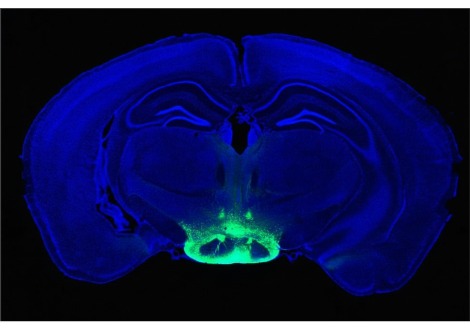

لا يزال الباحثون يبحثون في كيفية تسبب التلوث في الإصابة بمرض باركنسون ، لكن الدراسات تشير إلى أن الناس غالبًا ما يفقدون حاسة الشم من 10 إلى 20 عامًا قبل أن يصابوا بالرعشة والأعراض الكلاسيكية الأخرى للمرض ، كما يقول دورسي. قد يؤدي استنشاق الملوثات والمواد الكيميائية إلى إتلاف نظام الشم قبل أن يبدأ الدماغ في التدهور.